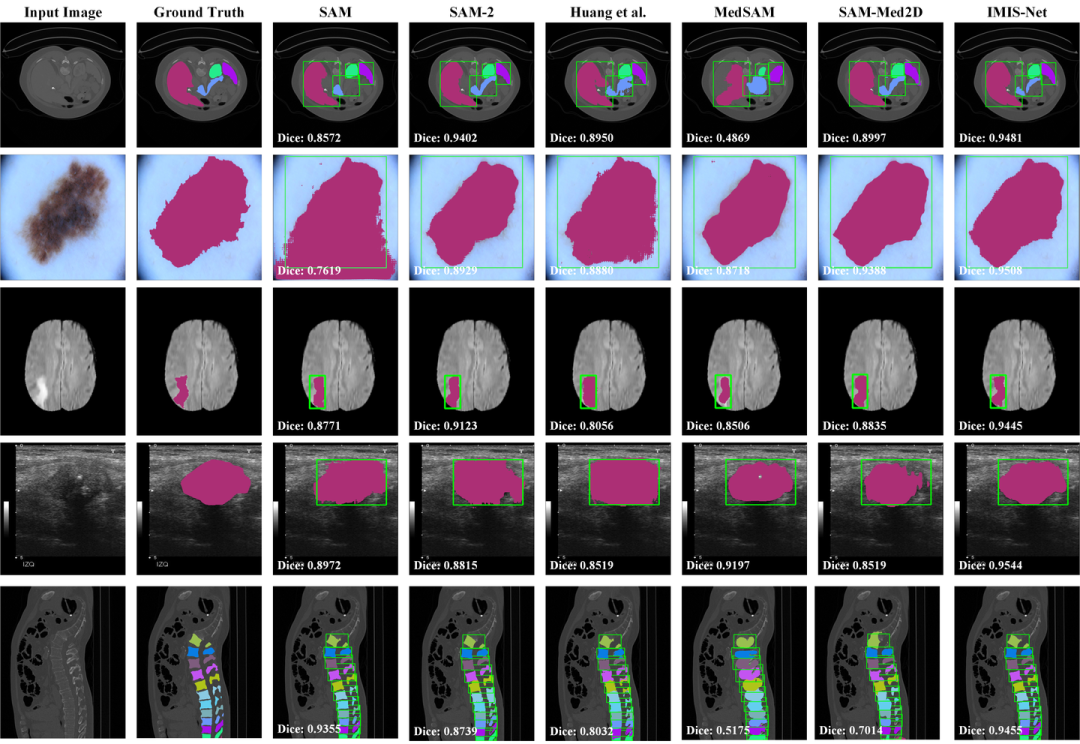

05 可视化结果

图8. 定性分析结果